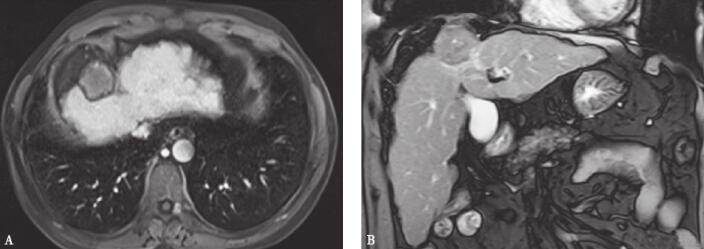

MRI检查肝顶部类圆形等T1等T2信号占位,轴位大小约3.83cm×3.52cm,考虑肝癌(图1)。

图1 术前检查MR图像